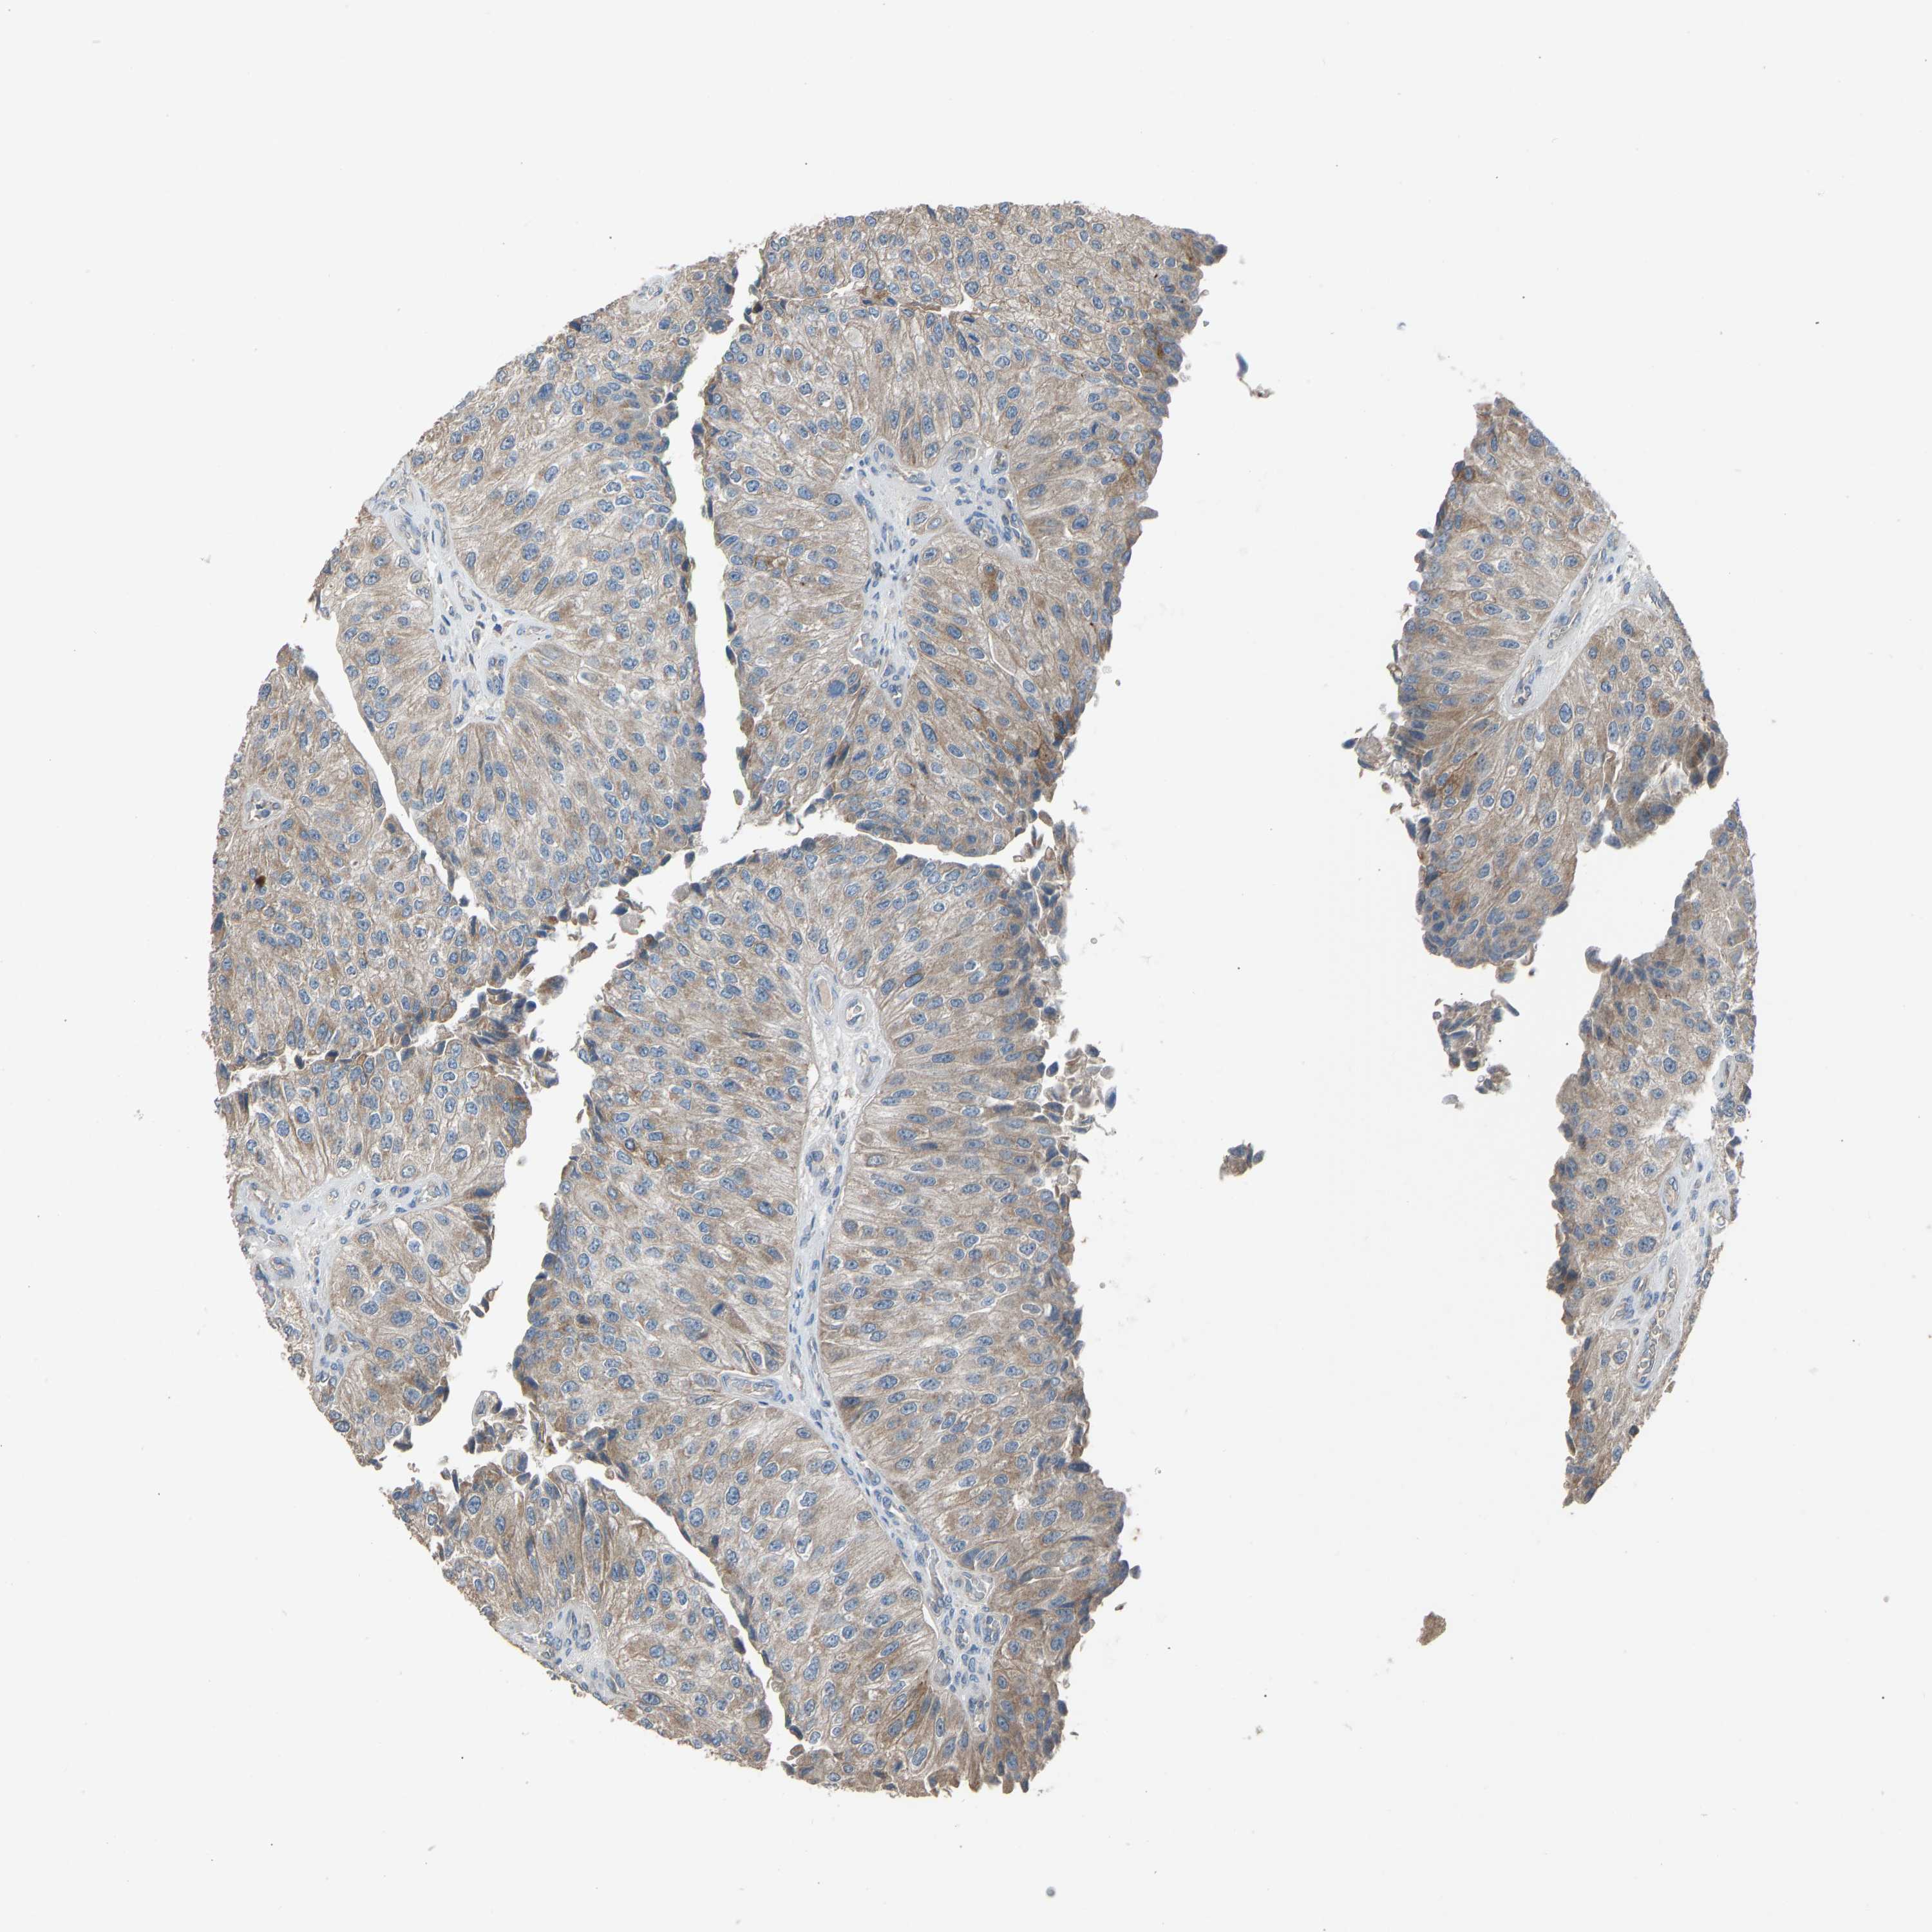

UROTHELIAL CANCER - Protein expressioni

A mouse-over function shows sample information and annotation data. Click on an image to view it in a full screen mode. Samples can be filtered based on level of antibody staining by selecting one or several of the following categories: high, medium, low and not detected. The assay and annotation is described here.

Antibody stainingi

Antibody staining in the annotated cell types in the current human tissue is reported as not detected, low, medium, or high, based on conventional immunohistochemistry profiling in selected tissues. This score is based on the combination of the staining intensity and fraction of stained cells.

Each image is clickable and will lead to virtual microscopy that enables deeper exploration of all samples and also displays staining intensity scores, fraction scores and subcellular localization as well as patient and tissue information for each sample.

Antibody HPA008257

Antibody CAB018971

Urothelial carcinoma, Low grade

Urothelial carcinoma, High grade